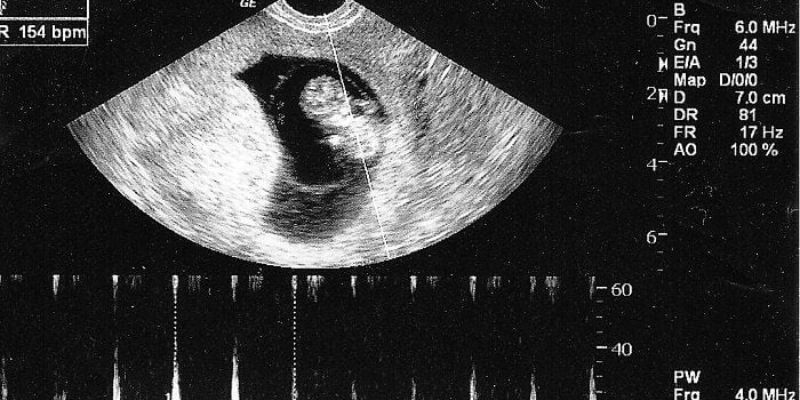

3. Nhịp Tim Thai 6 Tuần Bao Nhiêu Là Bình Thường?

Nhịp tim thai 6 tuần tuổi thường dao động từ 90 – 120 nhịp/phút. Tuy nhiên, tốc độ này có thể thay đổi và tăng dần trong các tuần tiếp theo. Nếu nhịp tim dưới 90 nhịp/phút, bác sĩ có thể chỉ định theo dõi để đảm bảo thai nhi phát triển bình thường.

4. Siêu Âm Tim Thai 6 Tuần

a. Phương Pháp Siêu Âm

Có hai phương pháp siêu âm phổ biến để kiểm tra tim thai:

- Siêu âm ổ bụng: Áp dụng cho những thai phụ có thành bụng mỏng, nhưng ở tuần thứ 6, phương pháp này có thể chưa phát hiện rõ nhịp tim.

- Siêu âm đầu dò âm đạo: Cho kết quả chính xác hơn về tim thai, đặc biệt là trong giai đoạn sớm của thai kỳ.